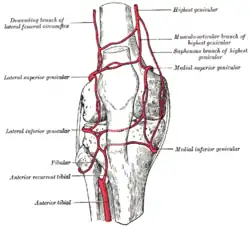

Arterien

Die arterielle Versorgung des Kniegelenkes erfolgt durch eine Vielzahl verschiedener Arterien, die untereinander anastomosieren und so ein dichtes Kollateralnetzwerk (Rete articulare genus) ausbilden. Zu ihnen zählen:

- Arteria descendens genus

- Arteria genus media

- Arteria superior lateralis genus

- Arteria superior medialis genus

- Arteria inferior lateralis genus

- Arteria inferior medialis genus